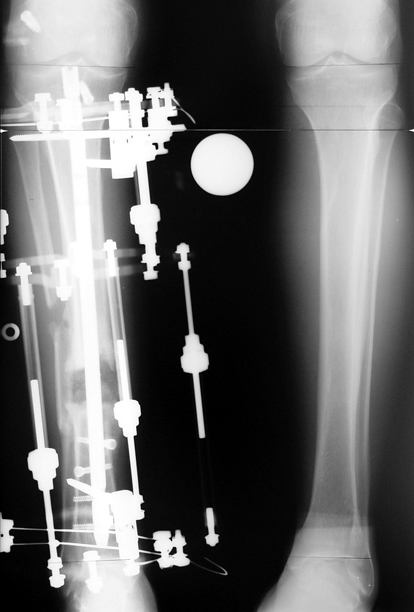

Recently, ilizarov techniques which is basis depend on distraction osteogenesis , bone segment transport or acute shortening after the resection at the site of pseudarthrosis combined with lengthening at another level of bone have been used. These treatment techniques may include some advantage for problems of infection, leg-length discrepancy, soft-tissue loss, and joint contracture.

Case 2